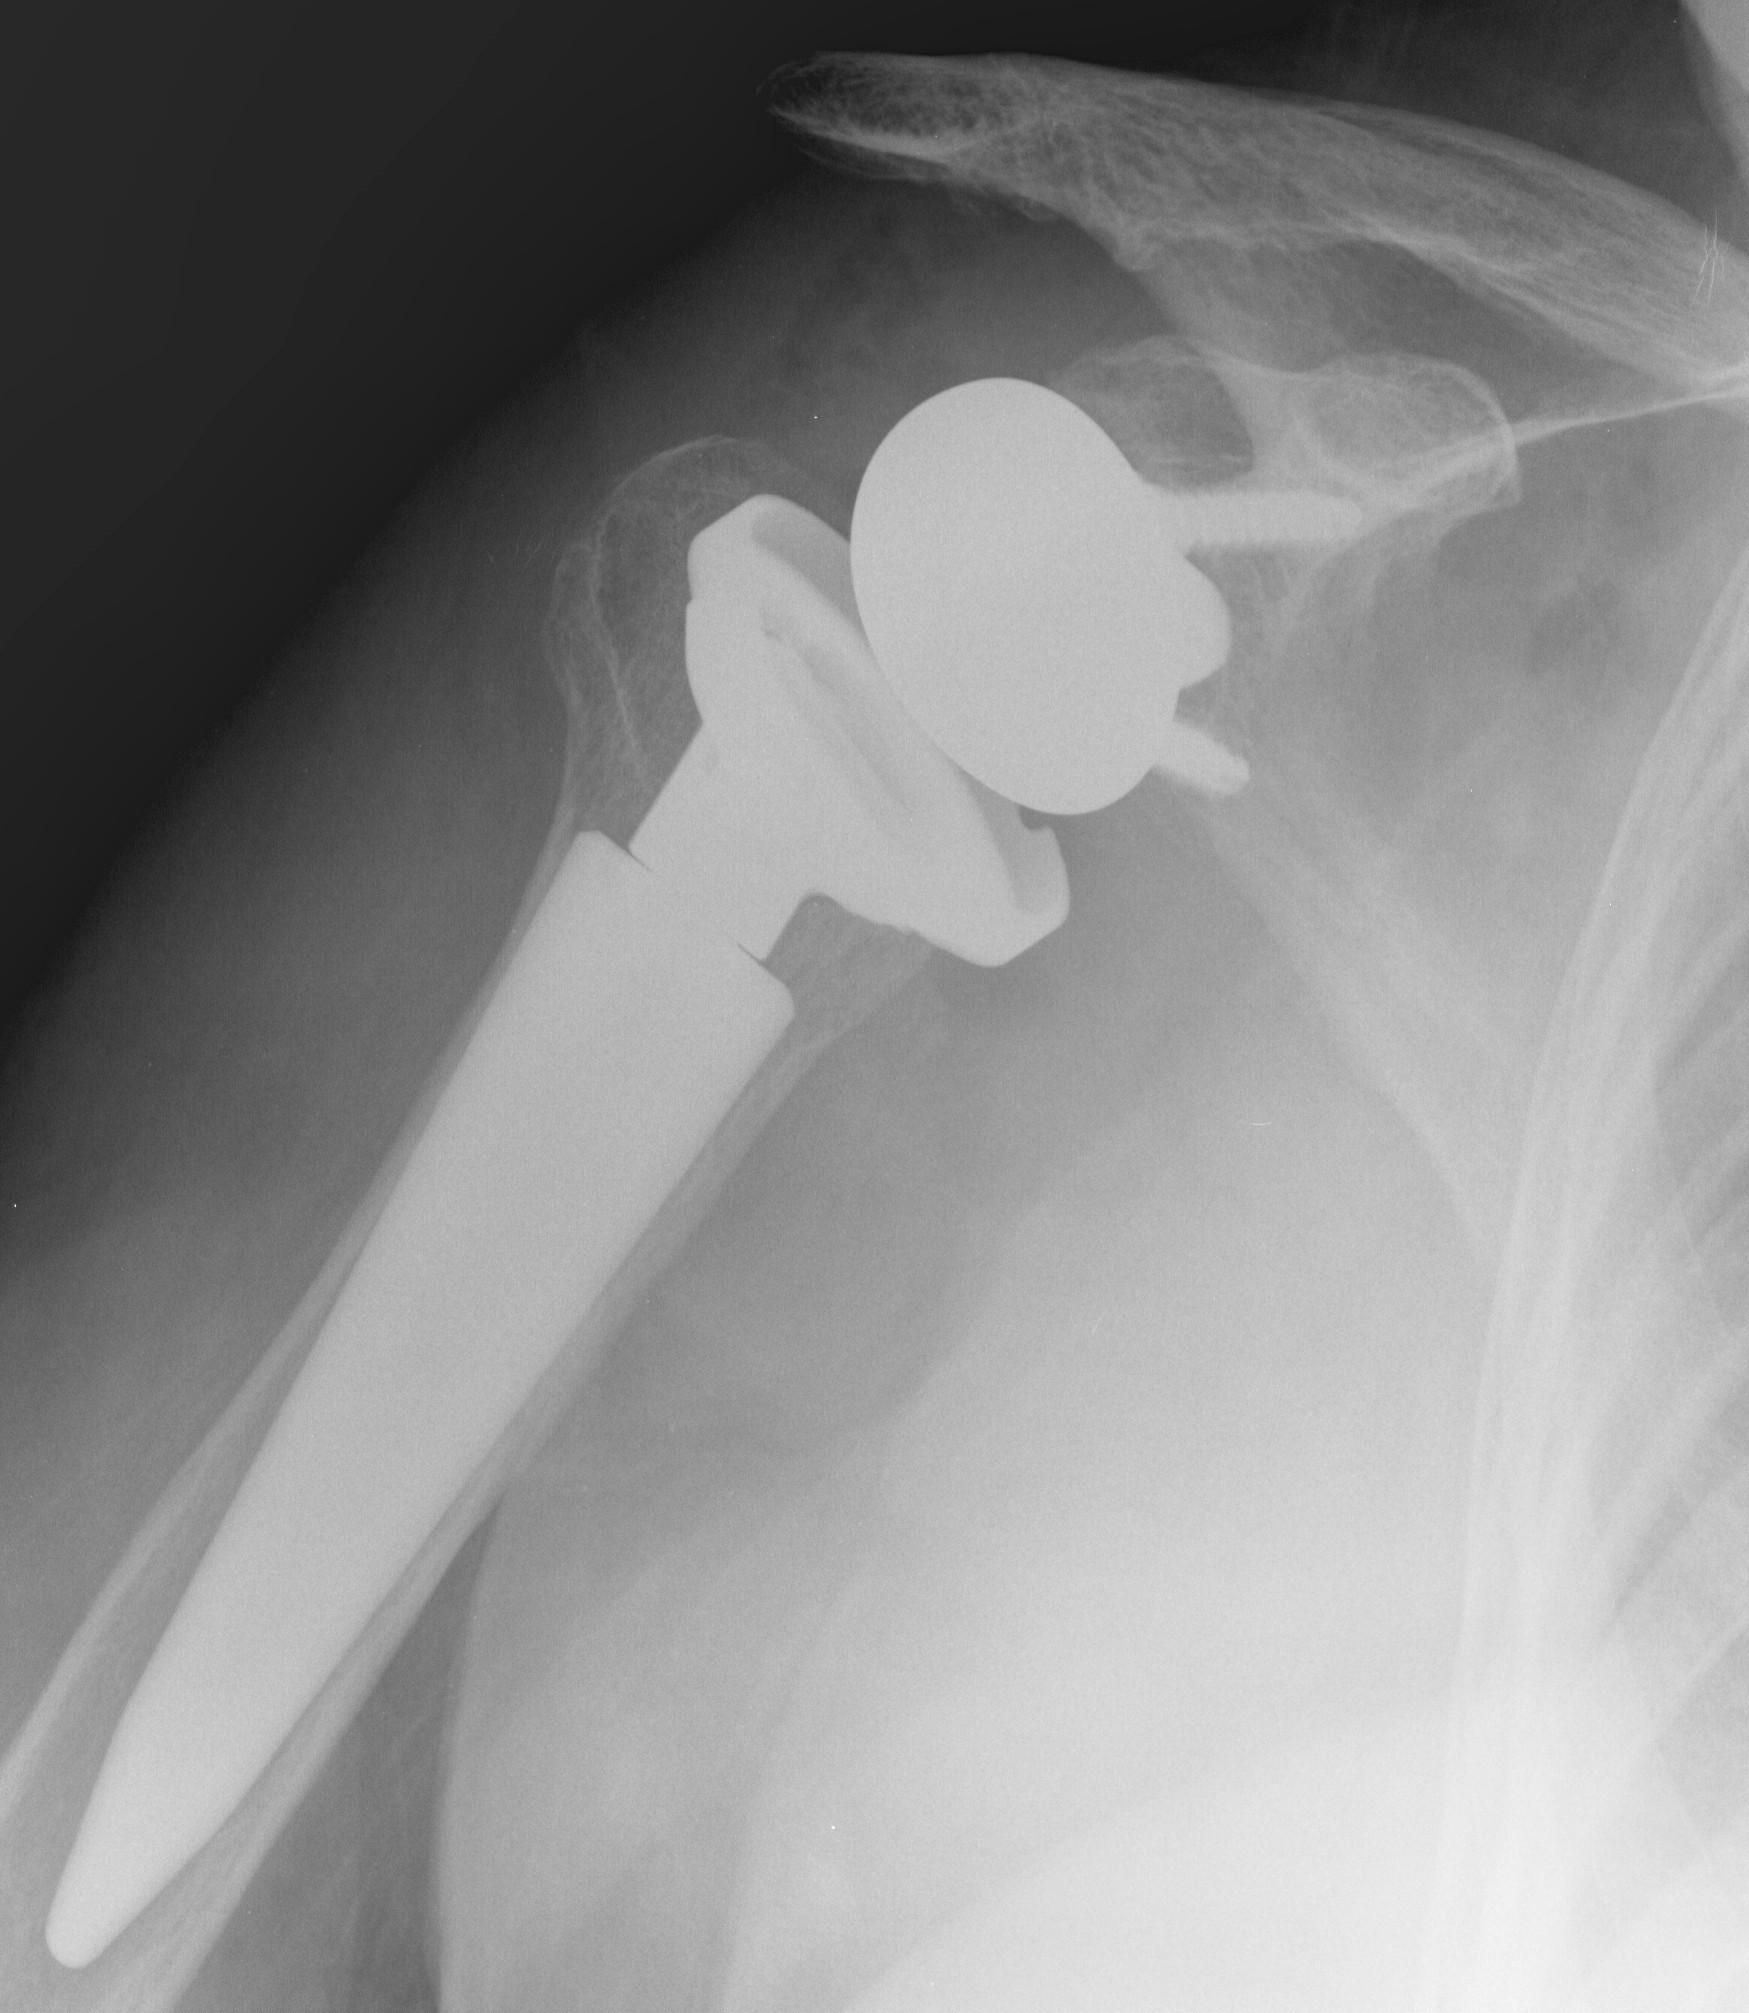

Inlay versus onlay

Inlay - humeral tray sits within a prepared cavity in humerus

Onlay - humeral tray sits on the prepared cut surface of the humerus

- systematic review of inlay versus only humeral components

- no difference in clinical outcomes or ROM

- inlay - increased scapular notching

- onlay - increased scapular spine fractures